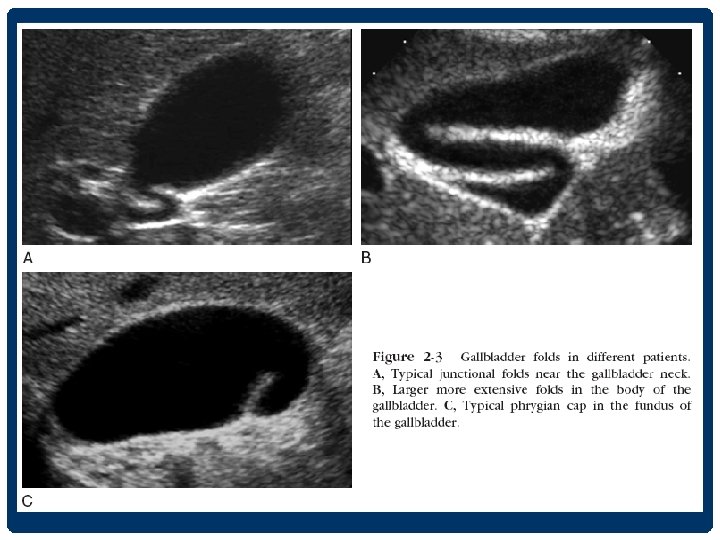

THE GALLBLADDER • อยใต interlobar fissure • ใชเปน landmark for identifying the junction between the left and right lobes of the liver • งดนำงดอาหาร ประมาณ 4 -6 ชวโมง adequate gallbladder distention + reduce upper abdominal bowel gas

CHARACTERISTICS OF THE NORMAL GALLBLADDER